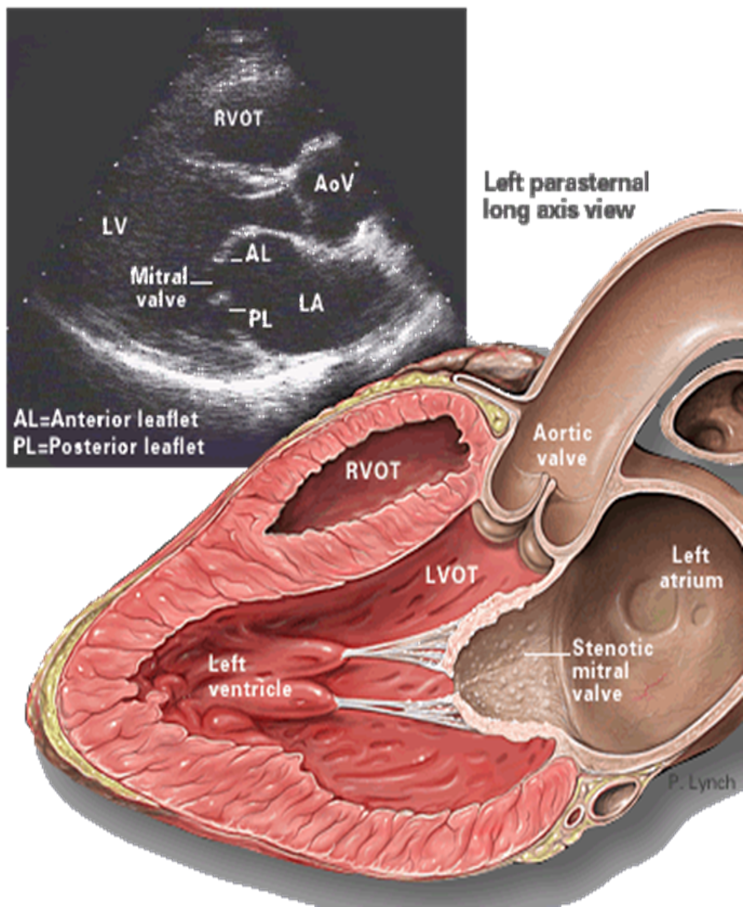

- TTE (Transthoracic echocardiography): best initial test to evaluate the mitral valve and quantify the anatomical extent of the stenosis.

Findings-

Reduced mitral valve area (MVA): ≤ 1.5 cm² (severe)

-

Thickened, calcified leaflets with commissural fusion

Increased mean diastolic pressure gradient across the mitral valve

RV dilation

LA enlargement

Evidence of pulmonary hypertension

Approach

All patients with suspected mitral stenosis should undergo transthoracic echocardiography (TTE).

- TTE is the most important test for diagnosing and guiding the treatment of mitral stenosis.